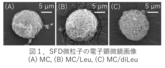

これらのSFD微粒子をマウスに気管内投与した後、モデル薬物として含有したインドシアニングリーン由来の近赤外蛍光をin vivo蛍光イメージング注3)により経時的に検出・解析した結果、MCを含む水溶液と同様にSFD微粒子でも、MCを含まないICG水溶液と比べて肺局所でより長時間にわたり強い蛍光が検出され、MC含有による肺内での薬物滞留性の向上効果が示唆されました (図2)。一方、肺障害性マーカーとして測定した体重・肺重量・動脈血酸素飽和度・気管支肺胞洗浄液注4)中の有核細胞数に変化はみられず、これらのSFD微粒子の高い安全性が窺えました。